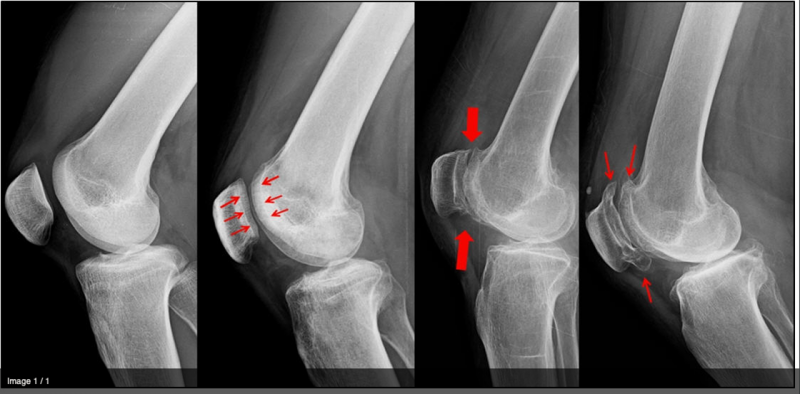

1) 슬개골 골절

슬개골 골절은 슬개골의 밑면을 보호해주는 관절 연골에 손상이 발생하게 되며 뼈가 붙는다 하더라도

관절 면은 틀어지게 되어 오랜 시간 후에 퇴행성 관절염이 발생하게 됩니다.

2) 형성이상(Dysplasia)

형성이상은 선천적으로 대퇴골 원위부의 과간부에 슬개골이 제대로 맞지 않는 경우 발생합니다.

이 때문에 무릎이 움직일 때 연골에 과도한 스트레스가 가해져 관절연골이 닳아 버리게 됩니다.